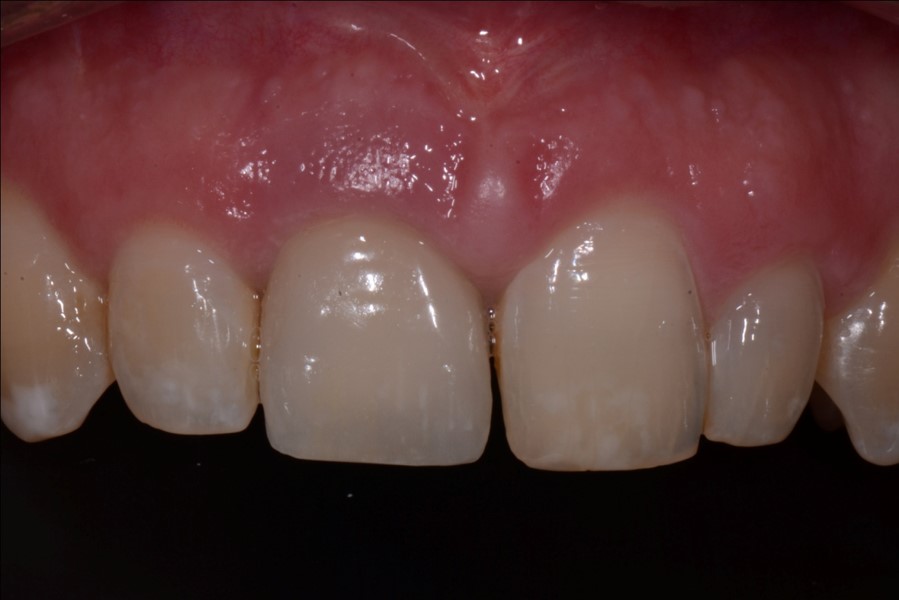

Fig 12. At 8 years post-treatment, the results of the minimally invasive approach remain an ideal esthetic implant placement, without visible damage or scar tissue from the flapless approach or connective tissue graft to thicken the biotype.

Figure 12

At 8 years post-treatment, implant bone levels were maintained as evidenced radiographically (Figure 11), with stable gingival margins and bone levels at the first thread of the fixture. There was minimal visible damage and scar tissue from the surgical approach to implant placement and tissue grafting to thicken the biotype. Despite the potential challenges, the use of growth factor technology and minimally invasive surgical techniques allowed the esthetic treatment goals for this case to be achieved for the long term (Figure 12).